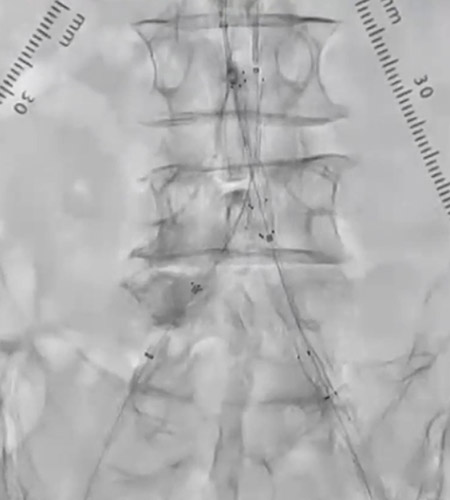

CIAにR2P Misago 9-40mmを留置。ステントproximalはCIA入口部ジャストに合わせたが、R2P Misagoはリリース時に位置ずれしにくく狙った位置に留置できた(図7)。